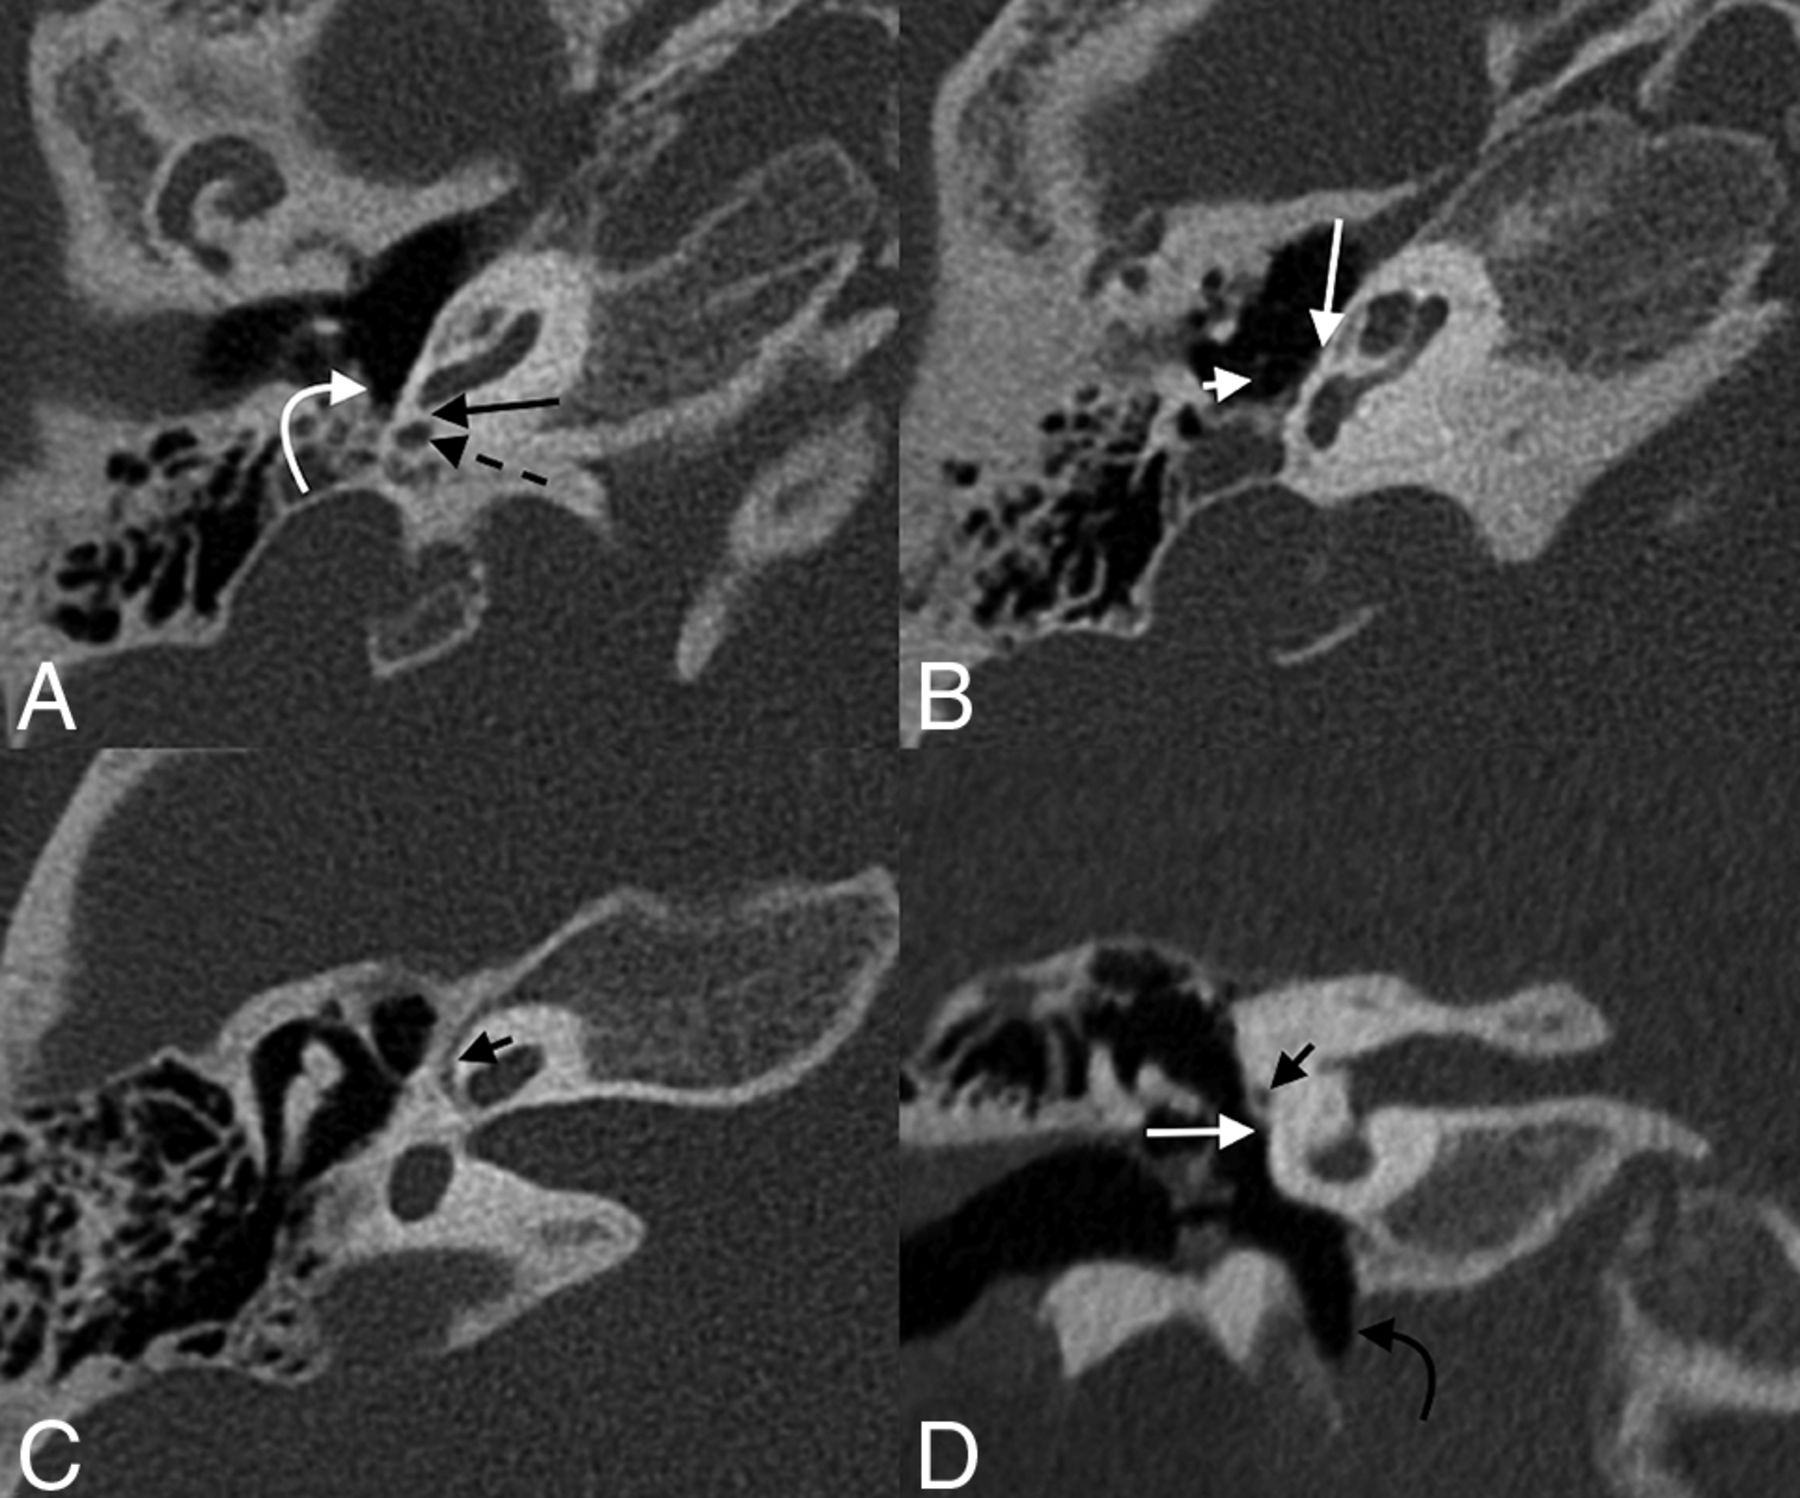

Labyrinthitis ossificans (LO) refers to ossification within the membranous labyrinth, most frequently occurring within the scala tympani.22 Typically, LO is secondary to inflammatory changes from infection such as suppurative otitis media, labyrinthitis, or meningitis, though trauma and otosclerosis have also been indicated as inciting processes.23,24 In cases of LO associated with bacterial meningitis, the basal turn of the cochlea is often preferentially affected because infection may spread from the subarachnoid space through the cochlear aqueduct to the proximal scala tympani (though spread may also occur through the modiolus).25 In some cases, LO may involve the round window, involvement thought to occur when the inciting event is otitis media or meningitis that spreads through the round window along the scala tympani (Fig 7).26 The etiology of LO cannot be predicted on the basis of mineralization patterns seen on CT.27 LO is associated with the development of sensorineural hearing loss and may render cochlear implantation more challenging and outcomes less rewarding.28,29 Extensive LO may preclude the placement of a cochlear implant. Expected CT findings of LO involving the round window include thickening/high attenuation along the membrane, likely with coexistent ossific material in the basal turn of the cochlea or elsewhere in the membranous labyrinth. In the early stages of labyrinthitis, fibrosis may be evident only on heavily weighted T2 imaging, where low signal is seen within or partially replacing normally high-signal perilymph.

Labyrinthitis ossificans with round window involvement. Axial (A and B), Pöschl (C), and coronal (D) images of the left temporal bone of a 5-year-old with a history of prior tympanoplasty tube placements. Labyrinthitis ossificans is seen in the basal turn of the cochlea (straight arrows, A and D) with mineralization of the round window (curved arrows, B and C).

The appearance of otosclerosis on imaging depends on the disease phase. In the active (otospongiotic) stage, the affected bone surrounding the round window will appear lucent and demineralized (Fig 8).36,37 Later on, these areas are replaced by sclerotic bone during the nonactive (otosclerotic) stage.37 As this replacement occurs, the round window membrane may become thickened or irregular. Heaped-up osseous plaques may narrow the round window or adjacent niche.34

Otosclerosis with round window involvement. Axial (A), Pöschl (B), and coronal (C) images of the right temporal bone demonstrate bony changes compatible with otosclerosis adjacent to the round window, with marked narrowing of the round window niche (arrows).

High-riding jugular bulbs, dehiscent bulbs, and jugular diverticula are often asymptomatic.41 However, they may also present with pulsatile tinnitus or, less commonly, conductive hearing loss, likely related to encroachment by the bulb on the round window, ossicular chain, or tympanic membrane (Fig 9).41,42 The incidence in which the round window membrane is specifically involved is rare; 1 histologic analysis of temporal bones identified 2 such cases in 1579 specimens (0.1%).43

Jugular bulb anomalies. Coronal (A), Pöschl (B), and axial (C) images demonstrate a high-riding jugular bulb (asterisk) that extends into the round window niche (straight black arrows). The bony margins overlying the jugular bulb within the middle window are markedly thinned, compatible with dehiscence (white arrows).

Intralabyrinthine schwannoma with involvement of the round window. Axial (A and B) and coronal (C) contrast-enhanced T1WI shows an avidly enhancing mass in the left cochlea (straight arrows) and vestibule (curved arrow), compatible with a schwannoma. The mass extends through the round window membrane and into the round window niche (dashed arrows), better demonstrated on the follow-up axial (D), Pöschl (E), and coronal (F) CT images.

Jugulotympanic paragangliomas—comprising glomus jugulare and glomus tympanicum tumors—may also involve the round window.48,49 Glomus tympanicum tumors arise from the tympanic nerve (Jacobson nerve) and grow within and along the cochlear promontory; if large enough, they may extend into and occlude the round window niche.48 Glomus jugulare tumors begin within the jugulare foramen. Although histologically benign, glomus jugulare tumors are locally destructive and can erode into adjacent middle ear structures such as the round window niche (Fig 11).

Glomus jugulare tumor with round window obstruction. Axial (A and B), Pöschl (C), and coronal (D) CT images of the right temporal bone show a permeative destructive mass centered in the right jugular foramen (asterisk), which extends into the right middle ear and fills the round window niche (curved arrows); opacification of the niche extends up to the round window membrane (straight arrow). Axial T2 sampling perfection with application-optimized contrasts by using different flip angle evolutions (SPACE sequence; Siemens, Erlangen, Germany) (E) and T1WI with gadolinium (F) also show the mass (asterisk) and round window niche occlusion (curved arrows).